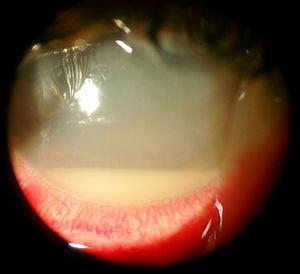

Hypopyon with hazy media

There is usually a history of recent eye surgery or a penetrating trauma to the eye. Symptoms include severe pain, vision loss, and intense redness of the conjunctiva. Hypopyon can be present and should be looked for on examination by a slit lamp. It can first present with the 'black dot sign' (Martin-Farina sign), where patients may report a small area of loss of vision that resembles a black dot or fly.